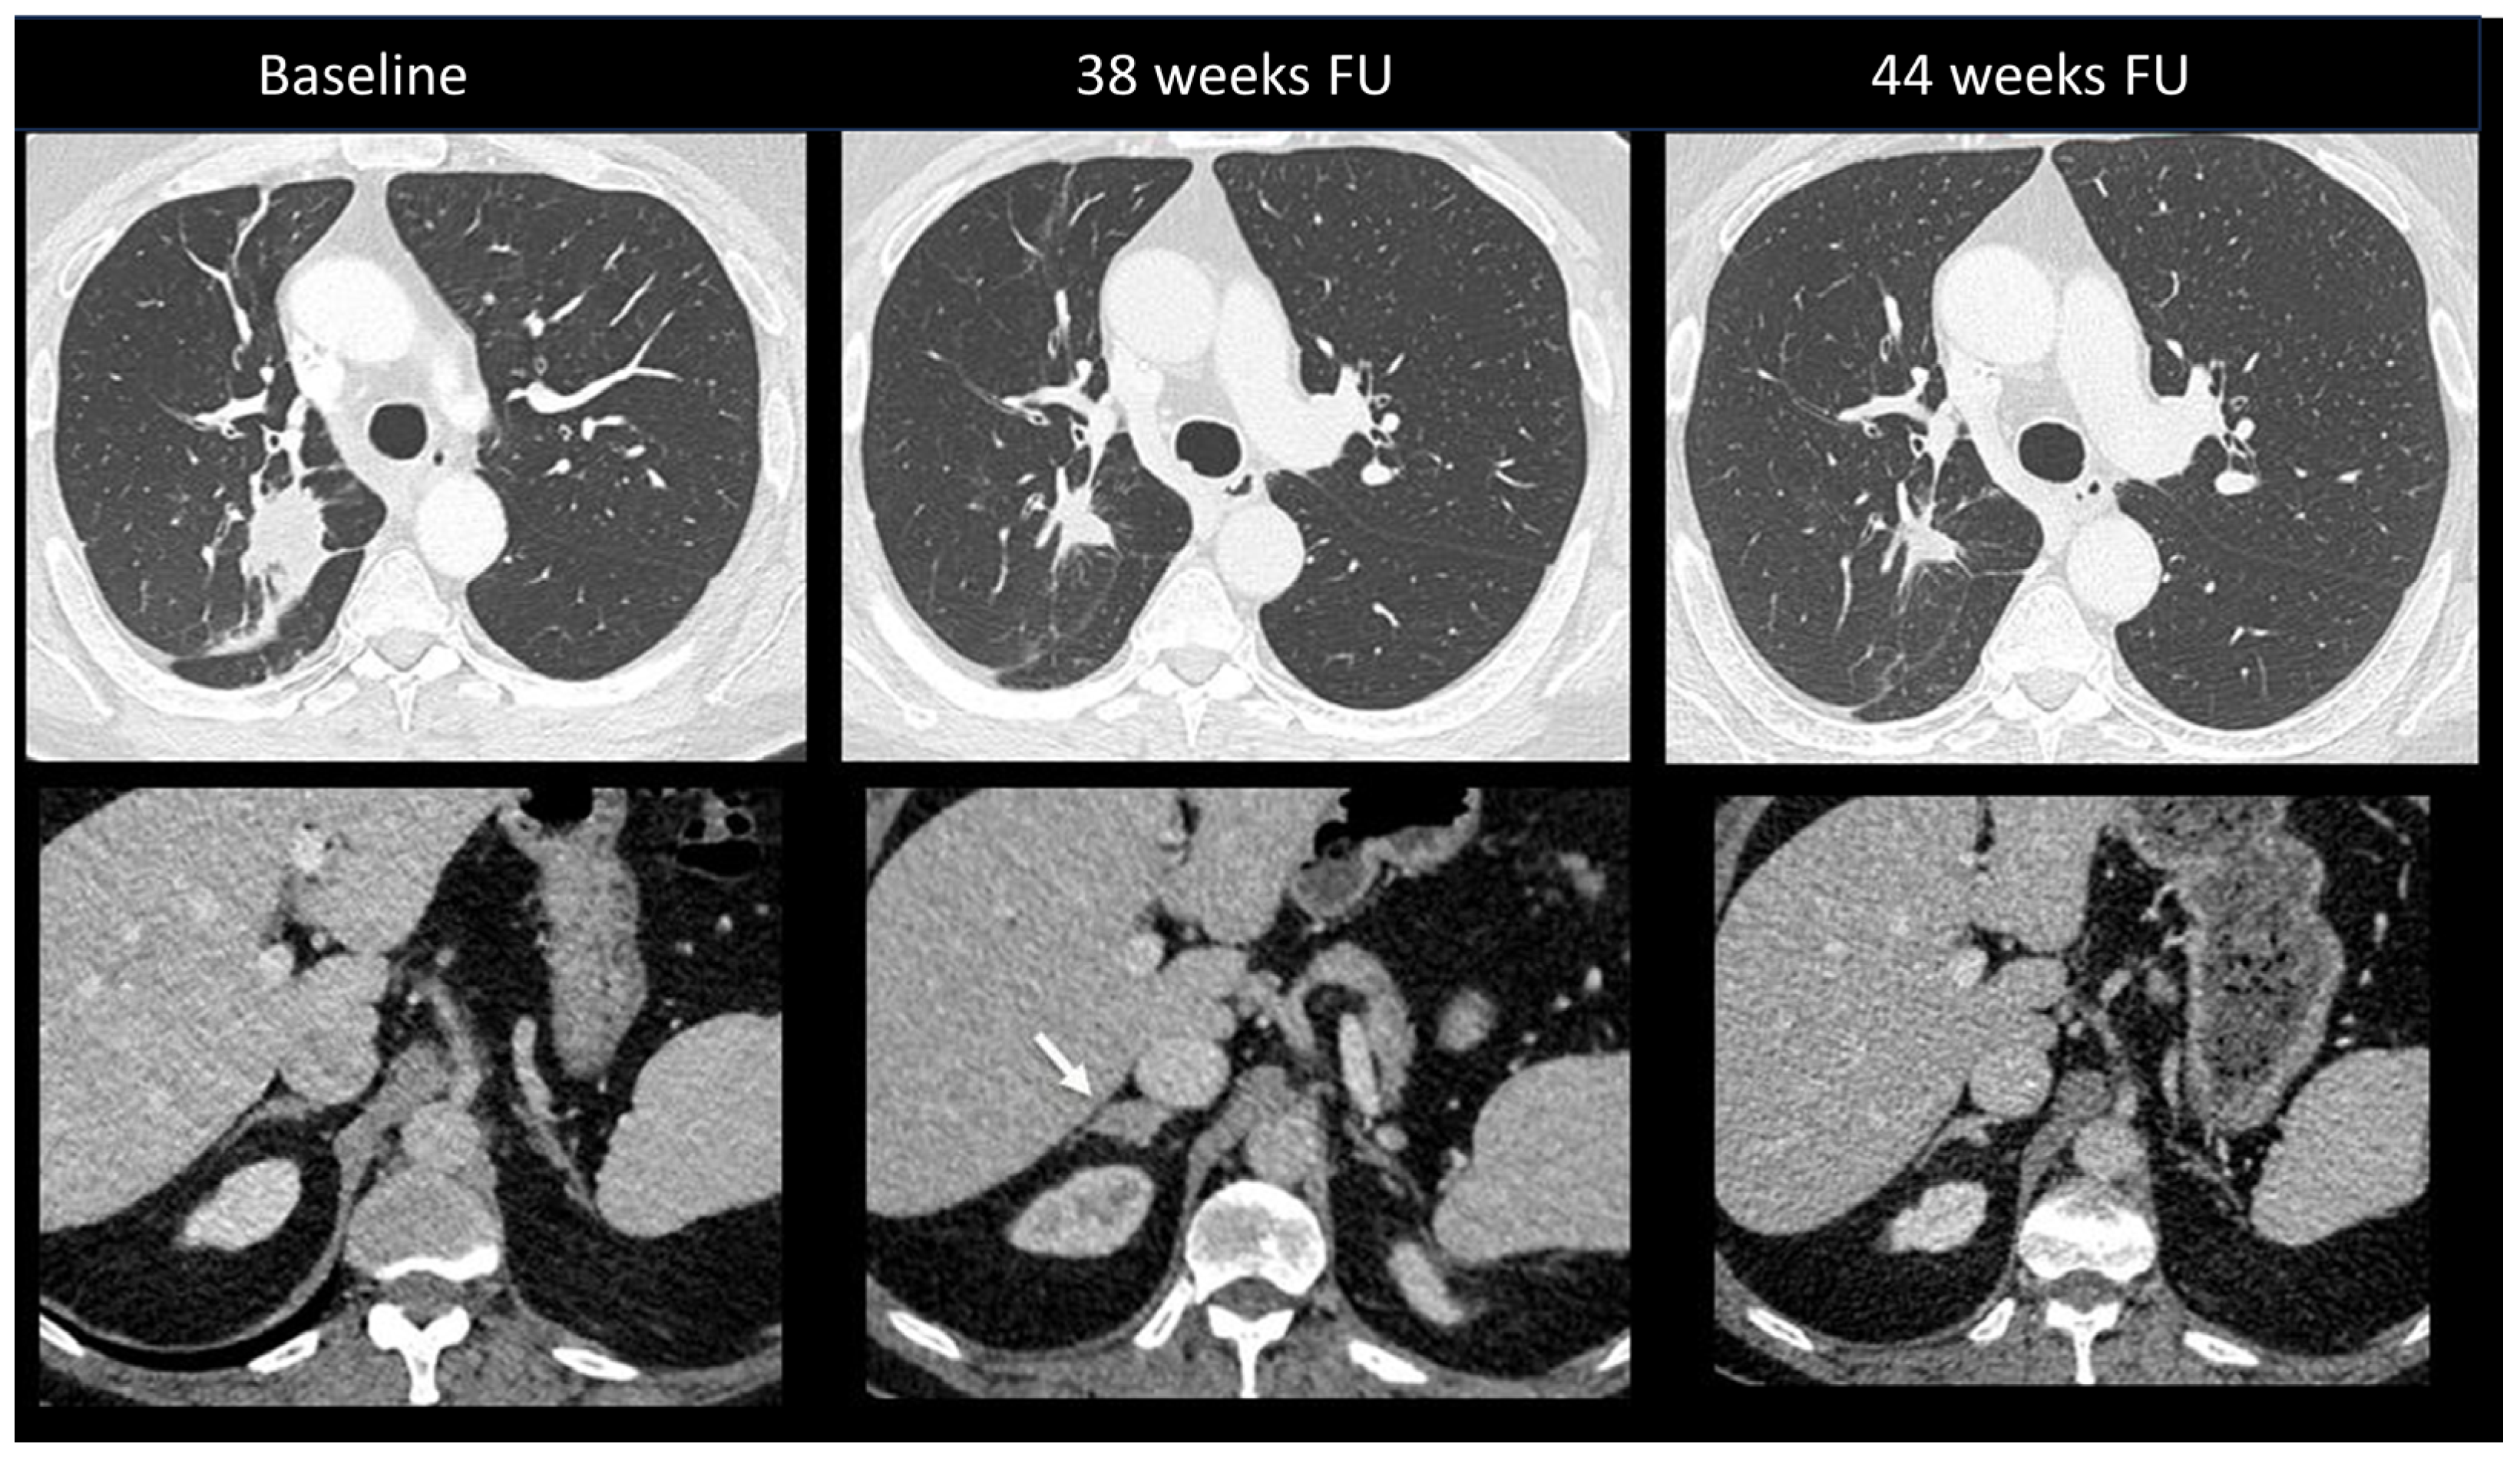

2.2.1. Ir-Pneumonitis

2.2.2. Sarcoidosis-Like Reaction